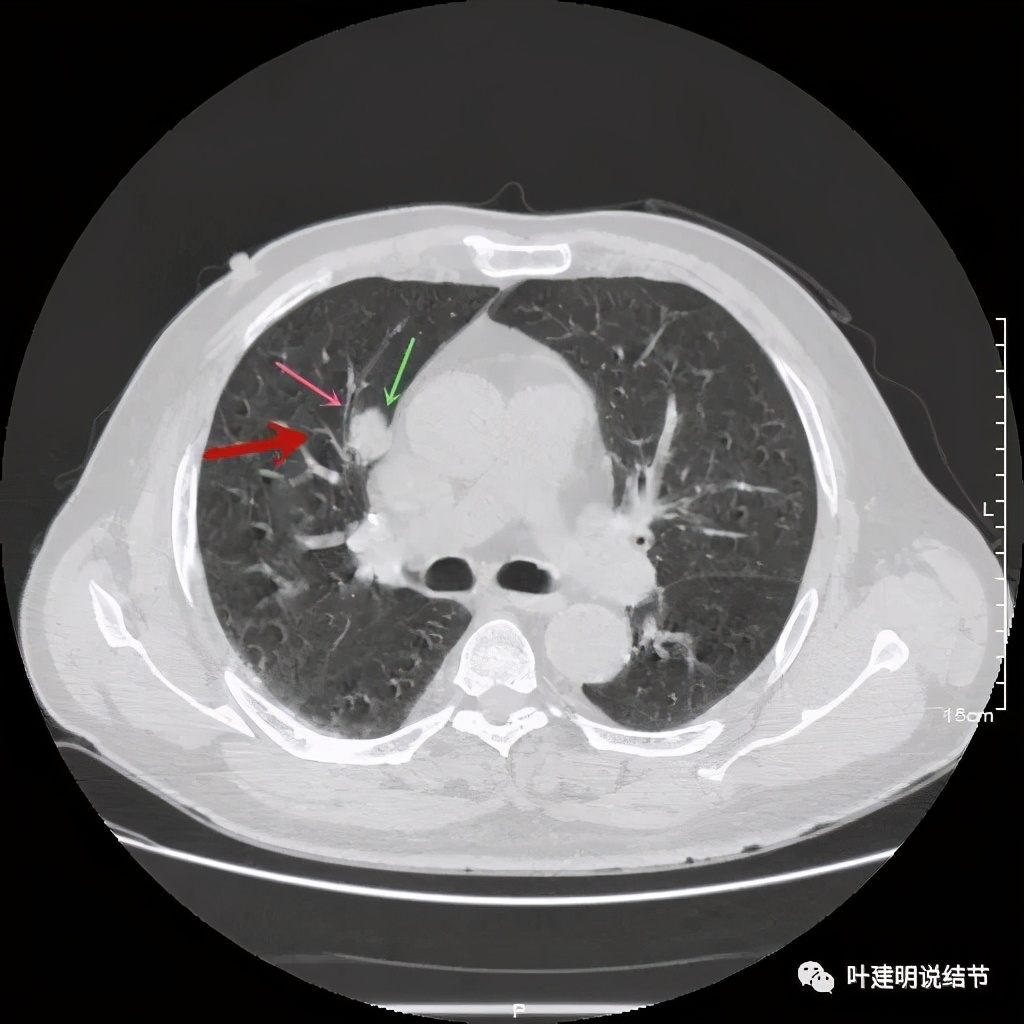

可见右上叶占位,我们现在知道了结果以后回头看,发现病灶的边缘在各个层面都是过于光滑(绿色箭头所示)。血管紧贴病灶边走行(桔色箭头所指),是不是有侵犯看不清楚,若是靶扫描加重建可能会更清楚点。支气管感觉也是贴着病灶走,但有的层面是不是截断,也不看的不太清楚。有的层面见局部有点状高密度(蓝色箭头所指),是不是错构瘤的局部钙化呢?若是纵隔窗又是如何?

上图示病灶密度不均,但边缘过于光滑(绿色);支气管似有截断(粉色);局部有点状钙化(蓝色)

上图也示病灶密度不均,但边缘过于光滑(绿色);支气管似有截断(粉色);局部有点状钙化(蓝色)